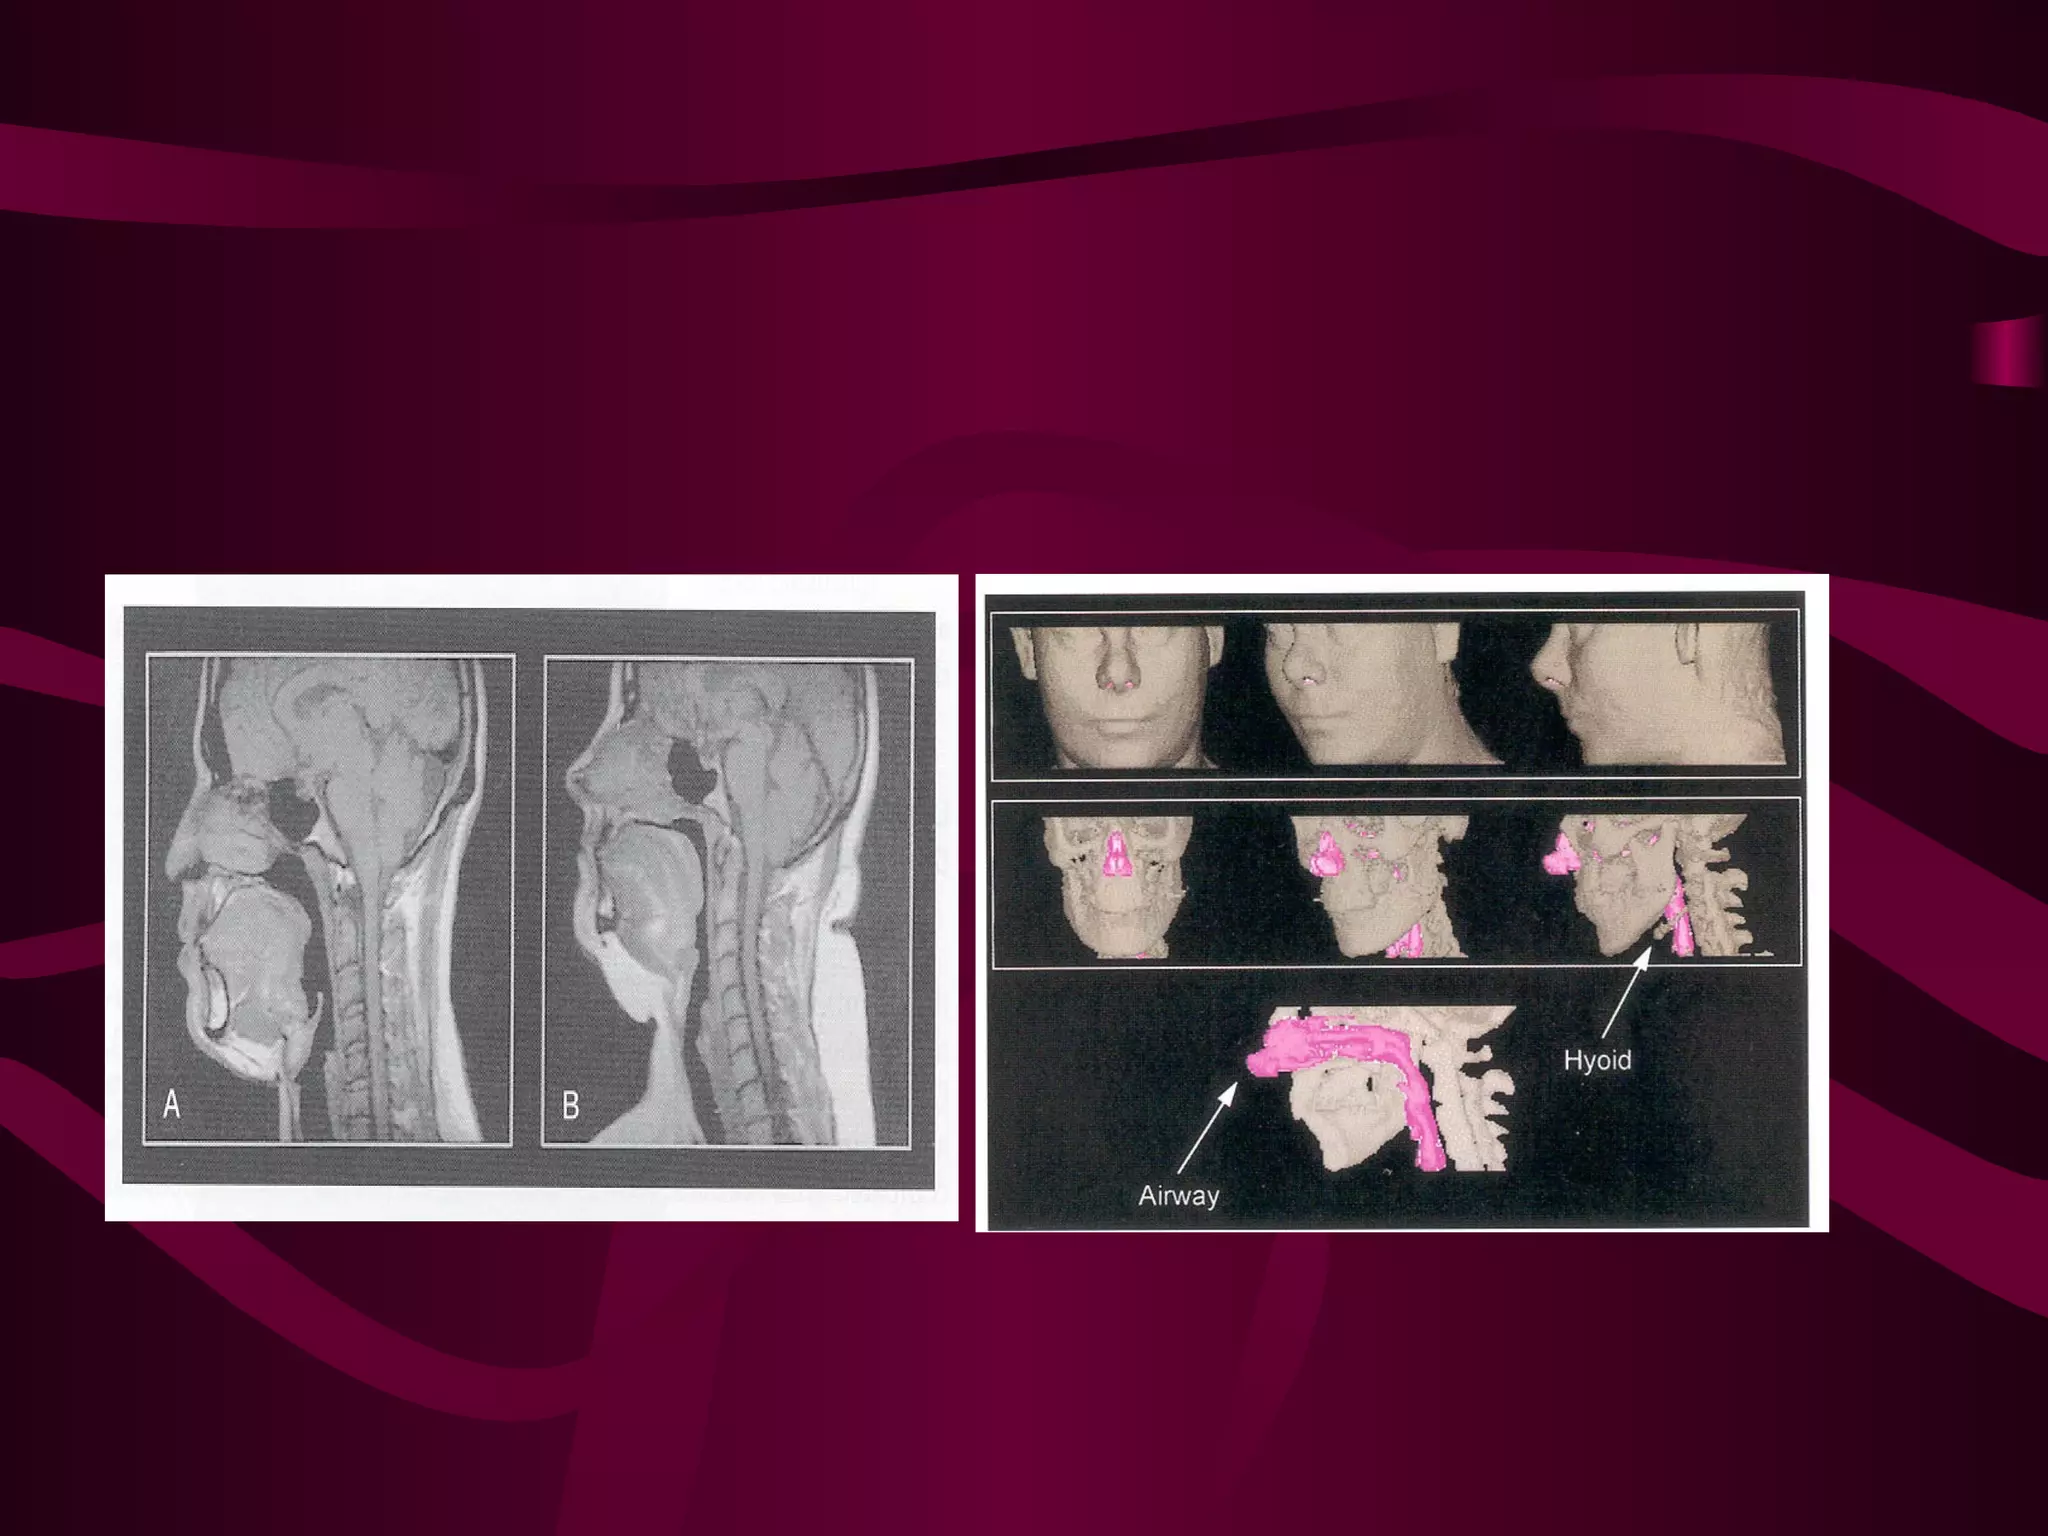

Imaging Studies:

CT& / MRI

Assessment of the upper airway

•   Fluoroscopy

•   Nasopharyngoscopy

•   Cephalometry

•   CT, Volumetric reconstruction

•   MRI

Assessment of theupper airway • Fluoroscopy • Nasopharyngoscopy • Cephalometry • CT, Volumetric reconstruction • MRI